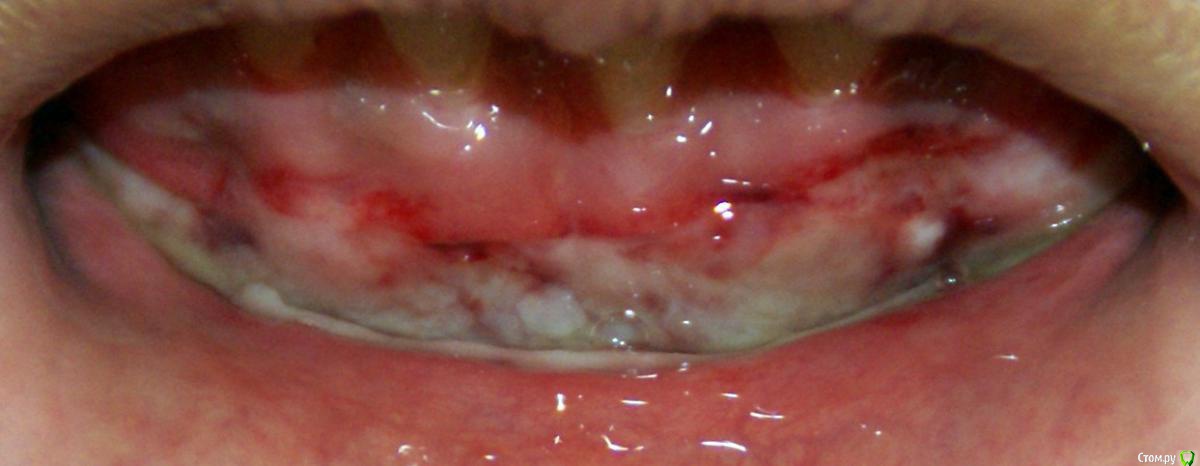

Irina_S Опубликовано 15 июня, 2017 Поделиться Опубликовано 15 июня, 2017 Здравствуйте, уважаемые специалисты! Заранее прошу прощения за не слишком качественные фото! Почти восемь месяцев назад мне была сделана вестибулопластика на нижней челюсти.За пять дней до операции ситуация во рту выглядела так: Для проведения операции были такие показания: Вот ещё описание самой операции, которая была 24 октября 2016 г.: Через шесть дней после операции: Ещё через шесть дней, 5 ноября: Прошла ещё неделя, 12 ноября: Следующий раз фото, к сожалению делалось через три с лишним недели, 4 декабря, в разных ракурсах: После этого визуальные изменения касались только уменьшения белёсых мест от разреза.Вот состояние на 10 июня этого года с разными вариантами оттягивания губы: По результатам заживления я не вижу разницы в глубине преддверия, ради чего и проводилась операция.К тому же всё время с момента операции присутствуют стягивающие ощущения и ощущение инородного тела в подбородке. Ответьте, пожалуйста, правильно ли была сделана операция вестибулопластики?Спасибо за внимание! Ссылка на комментарий

колесников Опубликовано 15 июня, 2017 Поделиться Опубликовано 15 июня, 2017 По уровню прикреплённой десны ситуация выглядит лучше,стабильнее чем до вмешательства. После вмешательств такого рода часто случаются рецидивы и неудачи,у Вас их нет. Но случаются и побочные "осложнения",в частности у Вас образовались тяжи в области клыков,которых раньше не было. Запргнозировать их оборазование зачастую невозможно. Это мягкие ткани,их можно попробовать "растянуть" или размягчить,делая миогимнастику,(надувая пузырь под губой),если это не поможет,дополнительная пластика по устранению этих тяжей. Ссылка на комментарий

Irina_S Опубликовано 16 июня, 2017 Автор Поделиться Опубликовано 16 июня, 2017 у Вас образовались тяжи в области клыков,которых раньше не было. А можно Вас попросить уточнить, что Вы называете тяжами?Под номером 1, под номером 2 или и то и другое вместе? Ещё вот такая хронология: 24 октября была сделана вестибулопластика, 28-го сняли швы, до 13 ноября я касалась кончиком языка "кармана" в глубине линии разреза, отметила это на фото, чтобы было понятно, о чём речь. 14 ноября проводилась обработка зубов с помощью аппарата Вектор и были заложены саморассасывающиеся лечебные повязки на обе челюсти, в том числе и в этот "карман". В этот день увидела, что "карман" визуально склеился из-за заложенной повязки, и я перестала на несколько дней делать упражнения с надуванием губ и касанием кончиком языка.А потом этот "карман" исчез и в итоге получилась поверхность, обозначенная на первой картинке под номером 3. Вопрос: мне не надо было допускать срастания двух поверхностей слизистой, чтобы этот "карман" остался, или его исчезновение и должно было произойти в процессе заживления? (думаю, что это срастание и вызвало ощущение стягивания и уплотнения внутри подбородка в виде инородного тела) Ссылка на комментарий